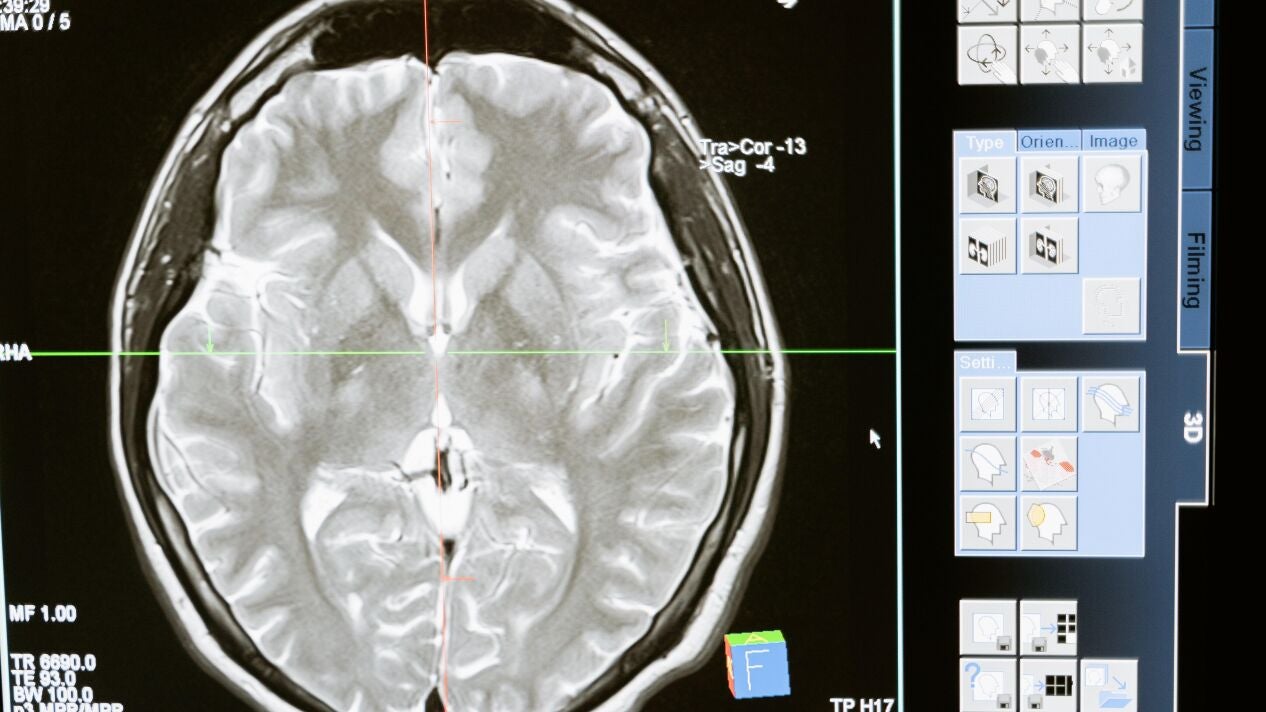

El cerebro de la mujer reduce su tamaño durante el embarazo y vuelve a recuperarlo en unos meses sin que eso sea necesariamente malo, según ha constatado una investigación que ha documentado los cambios neuro-anatómicos de una mujer antes, durante y después del embarazo. El estudio, recogido este lunes en la revista Nature Neurology, constituye el primer mapa cerebral de una mujer embarazada.

La nueva investigación específica estos cambios: una disminución generalizada del volumen de materia gris (cuerpos celulares que cumplen funciones mentales y cognitivas importantes) y del espesor cortical en la novena semana de embarazo.

La reducción de volumen afecta, sobre todo, a la llamada red neuronal por defecto, un sistema de áreas cerebrales conectadas entre sí que se activan cuando una persona está en reposo, según ha explicado en rueda de prensa una de las autoras, Emily Jacobs, investigadora de la Universidad de California-Santa Bárbara.

Por el contrario, los escáneres han mostrado un aumento de la materia blanca (fibras nerviosas responsables de facilitar la comunicación entre las regiones cerebrales), el volumen ventricular (crucial en la evaluación del riesgo cardíaco) y del líquido cefalorraquídeo, que actúa como un amortiguador que ayuda a proteger su cerebro y médula espinal de impactos o lesiones repentinas.

La investigación se ha llevado acabo mediante el análisis, apoyado en inteligencia artificial, de 26 resonancias magnéticas y análisis de sangre a una madre primeriza de 38 años desde tres semanas antes de la concepción (cuatro exploraciones), durante los tres trimestres del embarazo (15 exploraciones), hasta dos años después del parto (7 exploraciones) cuando finalizó el periodo de pruebas.